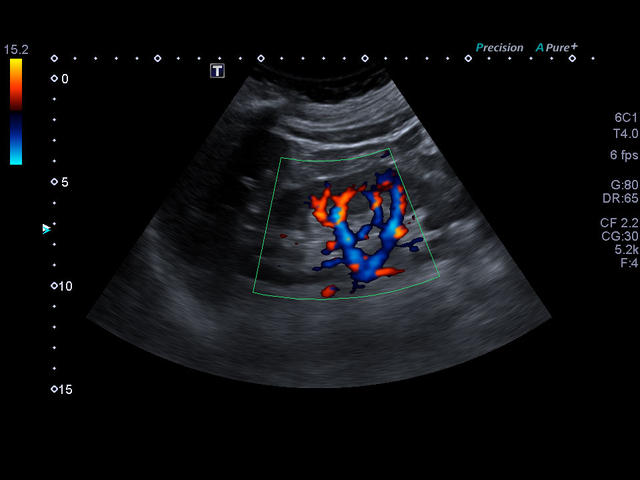

Xario 200 — это продуманная эргономика, впечатляющее качество изображения, отлаженный рабочий процесс и предельно высокая компактность. В Xario 200 цветовая доплеровская визуализация вышла на качественно новый уровень. Полностью интегрированная система управления данными пациентов и изображениями системы Xario обеспечивает удобный просмотр и простое управление исследованиями.

- Цветной, энергетический допплер - Colour Doppler Imaging/ Color Angio (CDI/CA).

- Одновременная обработка множества смежных ультразвуковых линий Precision Imaging